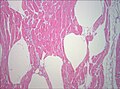

Biopsie de muscle examinée au microscope (colorée à l'haematoxyline-éosine, zoom 100×). Les vides blancs entre les fibres musculaires correspondent à des bulles de gaz.